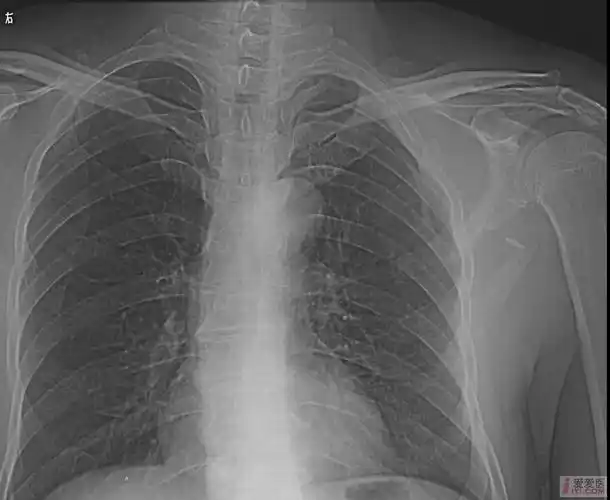

[请教]肩胛骨骨折